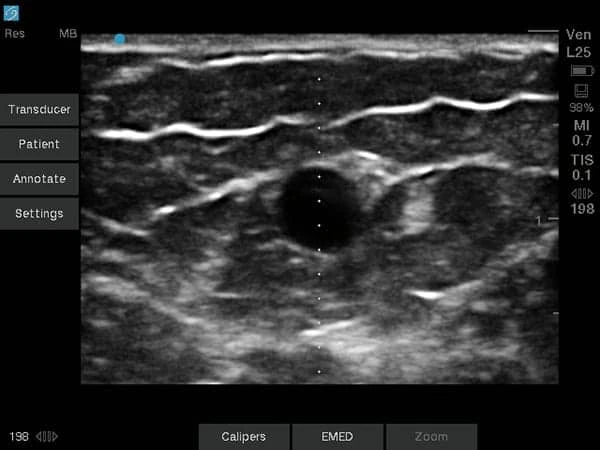

4D Ultrasound Scans

Experience a special bonding moment with your baby through advanced 4D ultrasound imaging. Our 4D scans provide real-time, lifelike images of your baby’s movements and facial expressions, creating a memorable and emotional experience for expectant parents and families.

- Real-time, lifelike images of your baby

- Best performed between 26–30 weeks of pregnancy

- Facial expressions, hand and foot movements (position permitting)

- Approximately 20-minute imaging session using advanced technology